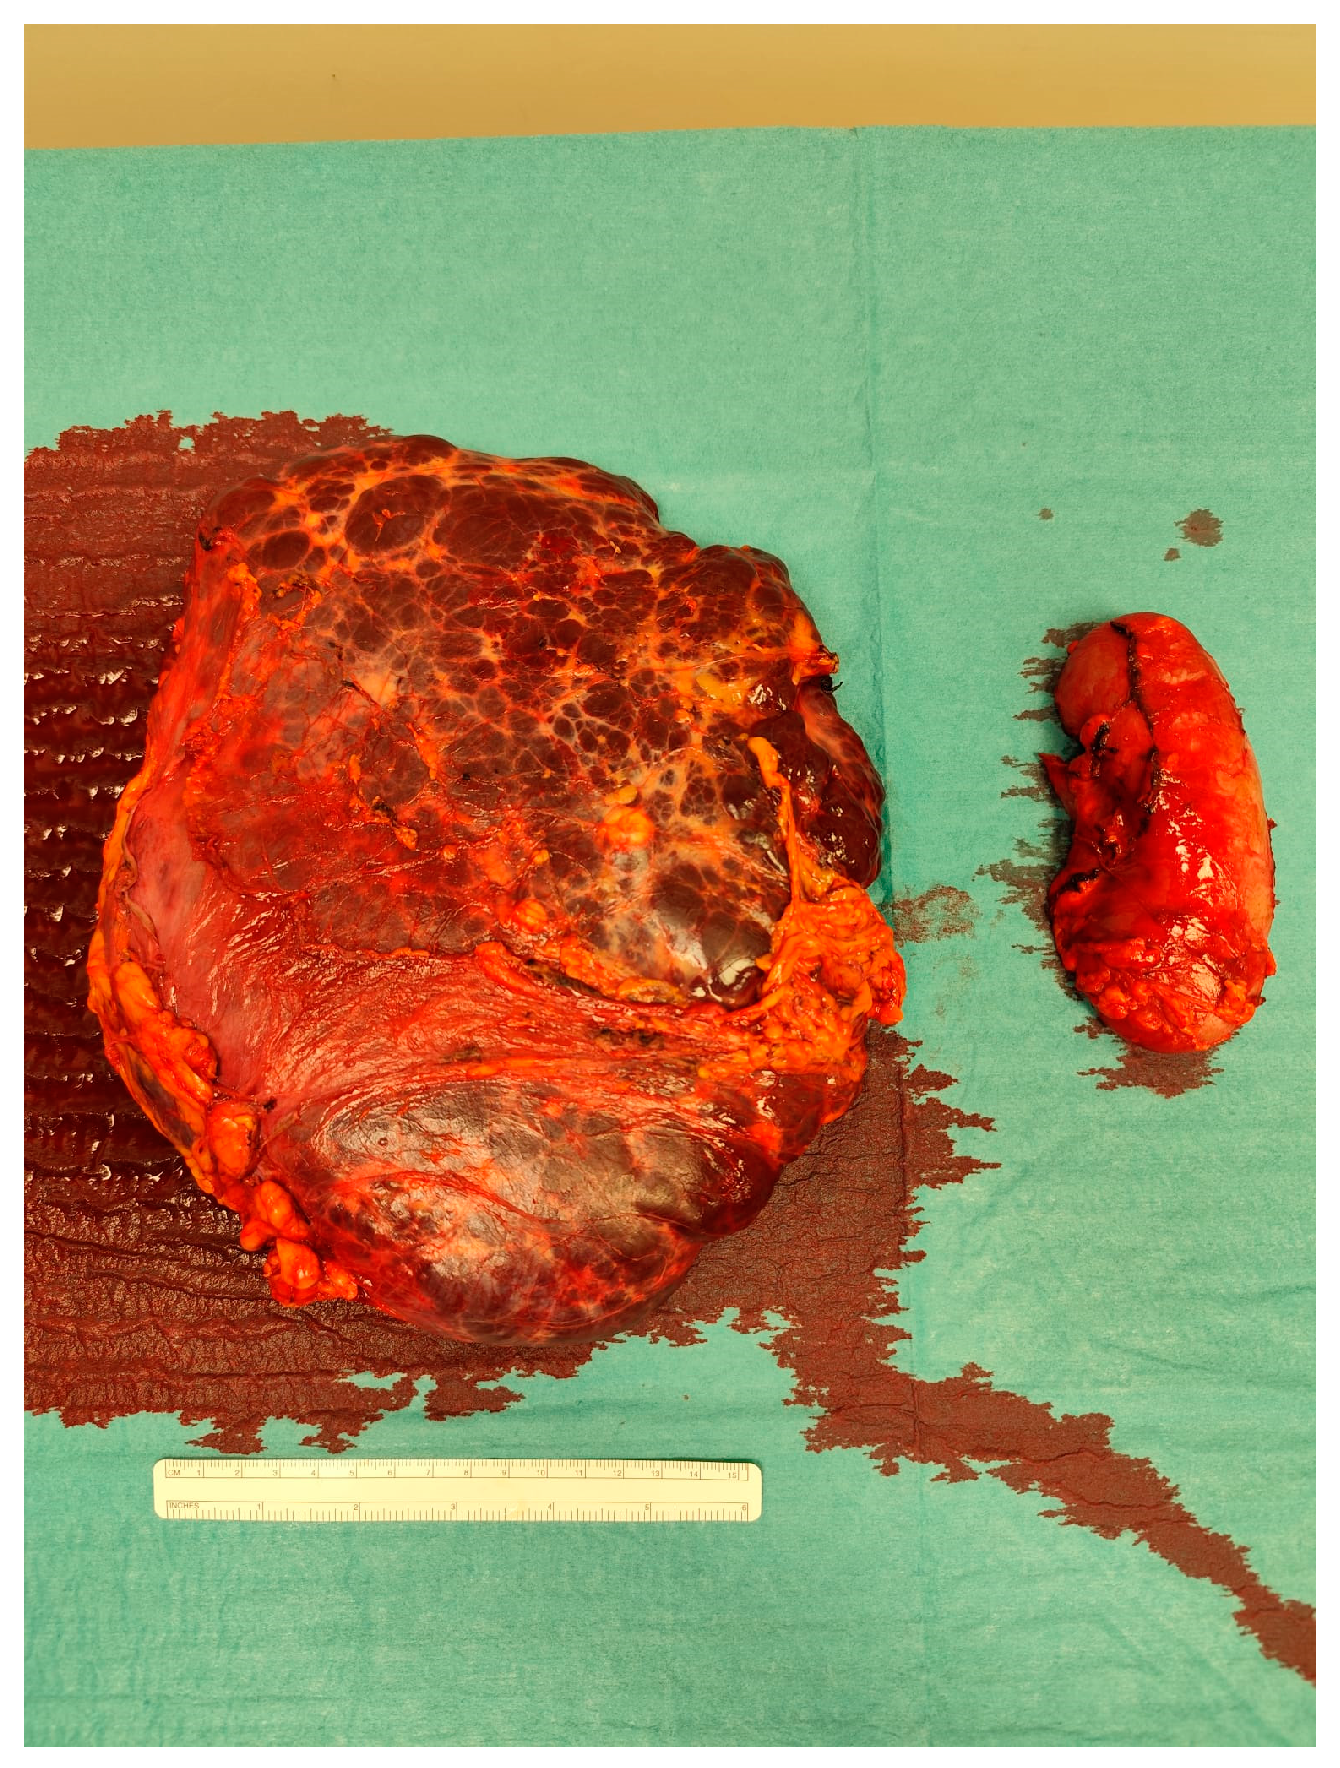

The case was discussed during the dedicated multi-disciplinary meeting and, due to the lesion considerable size and complex structure, as well as the inconclusive results of the biopsy, a surgical resection was advised. The procedure included “en bloc” removal of the left kidney and adrenal gland, both of which were tightly adherent to the mass (Figure 4 and Figure 5).

Postoperative pathological examination revealed a brownish, multiloculated cystic lesion measuring 18 x 17 x 30 cm, with areas of hemorrhage and multiple whitish calcified components. Subsequent analysis identified these calcifications as phleboliths, formed secondary to intralesional thrombotic events.

Figure 5. The resected specimen.